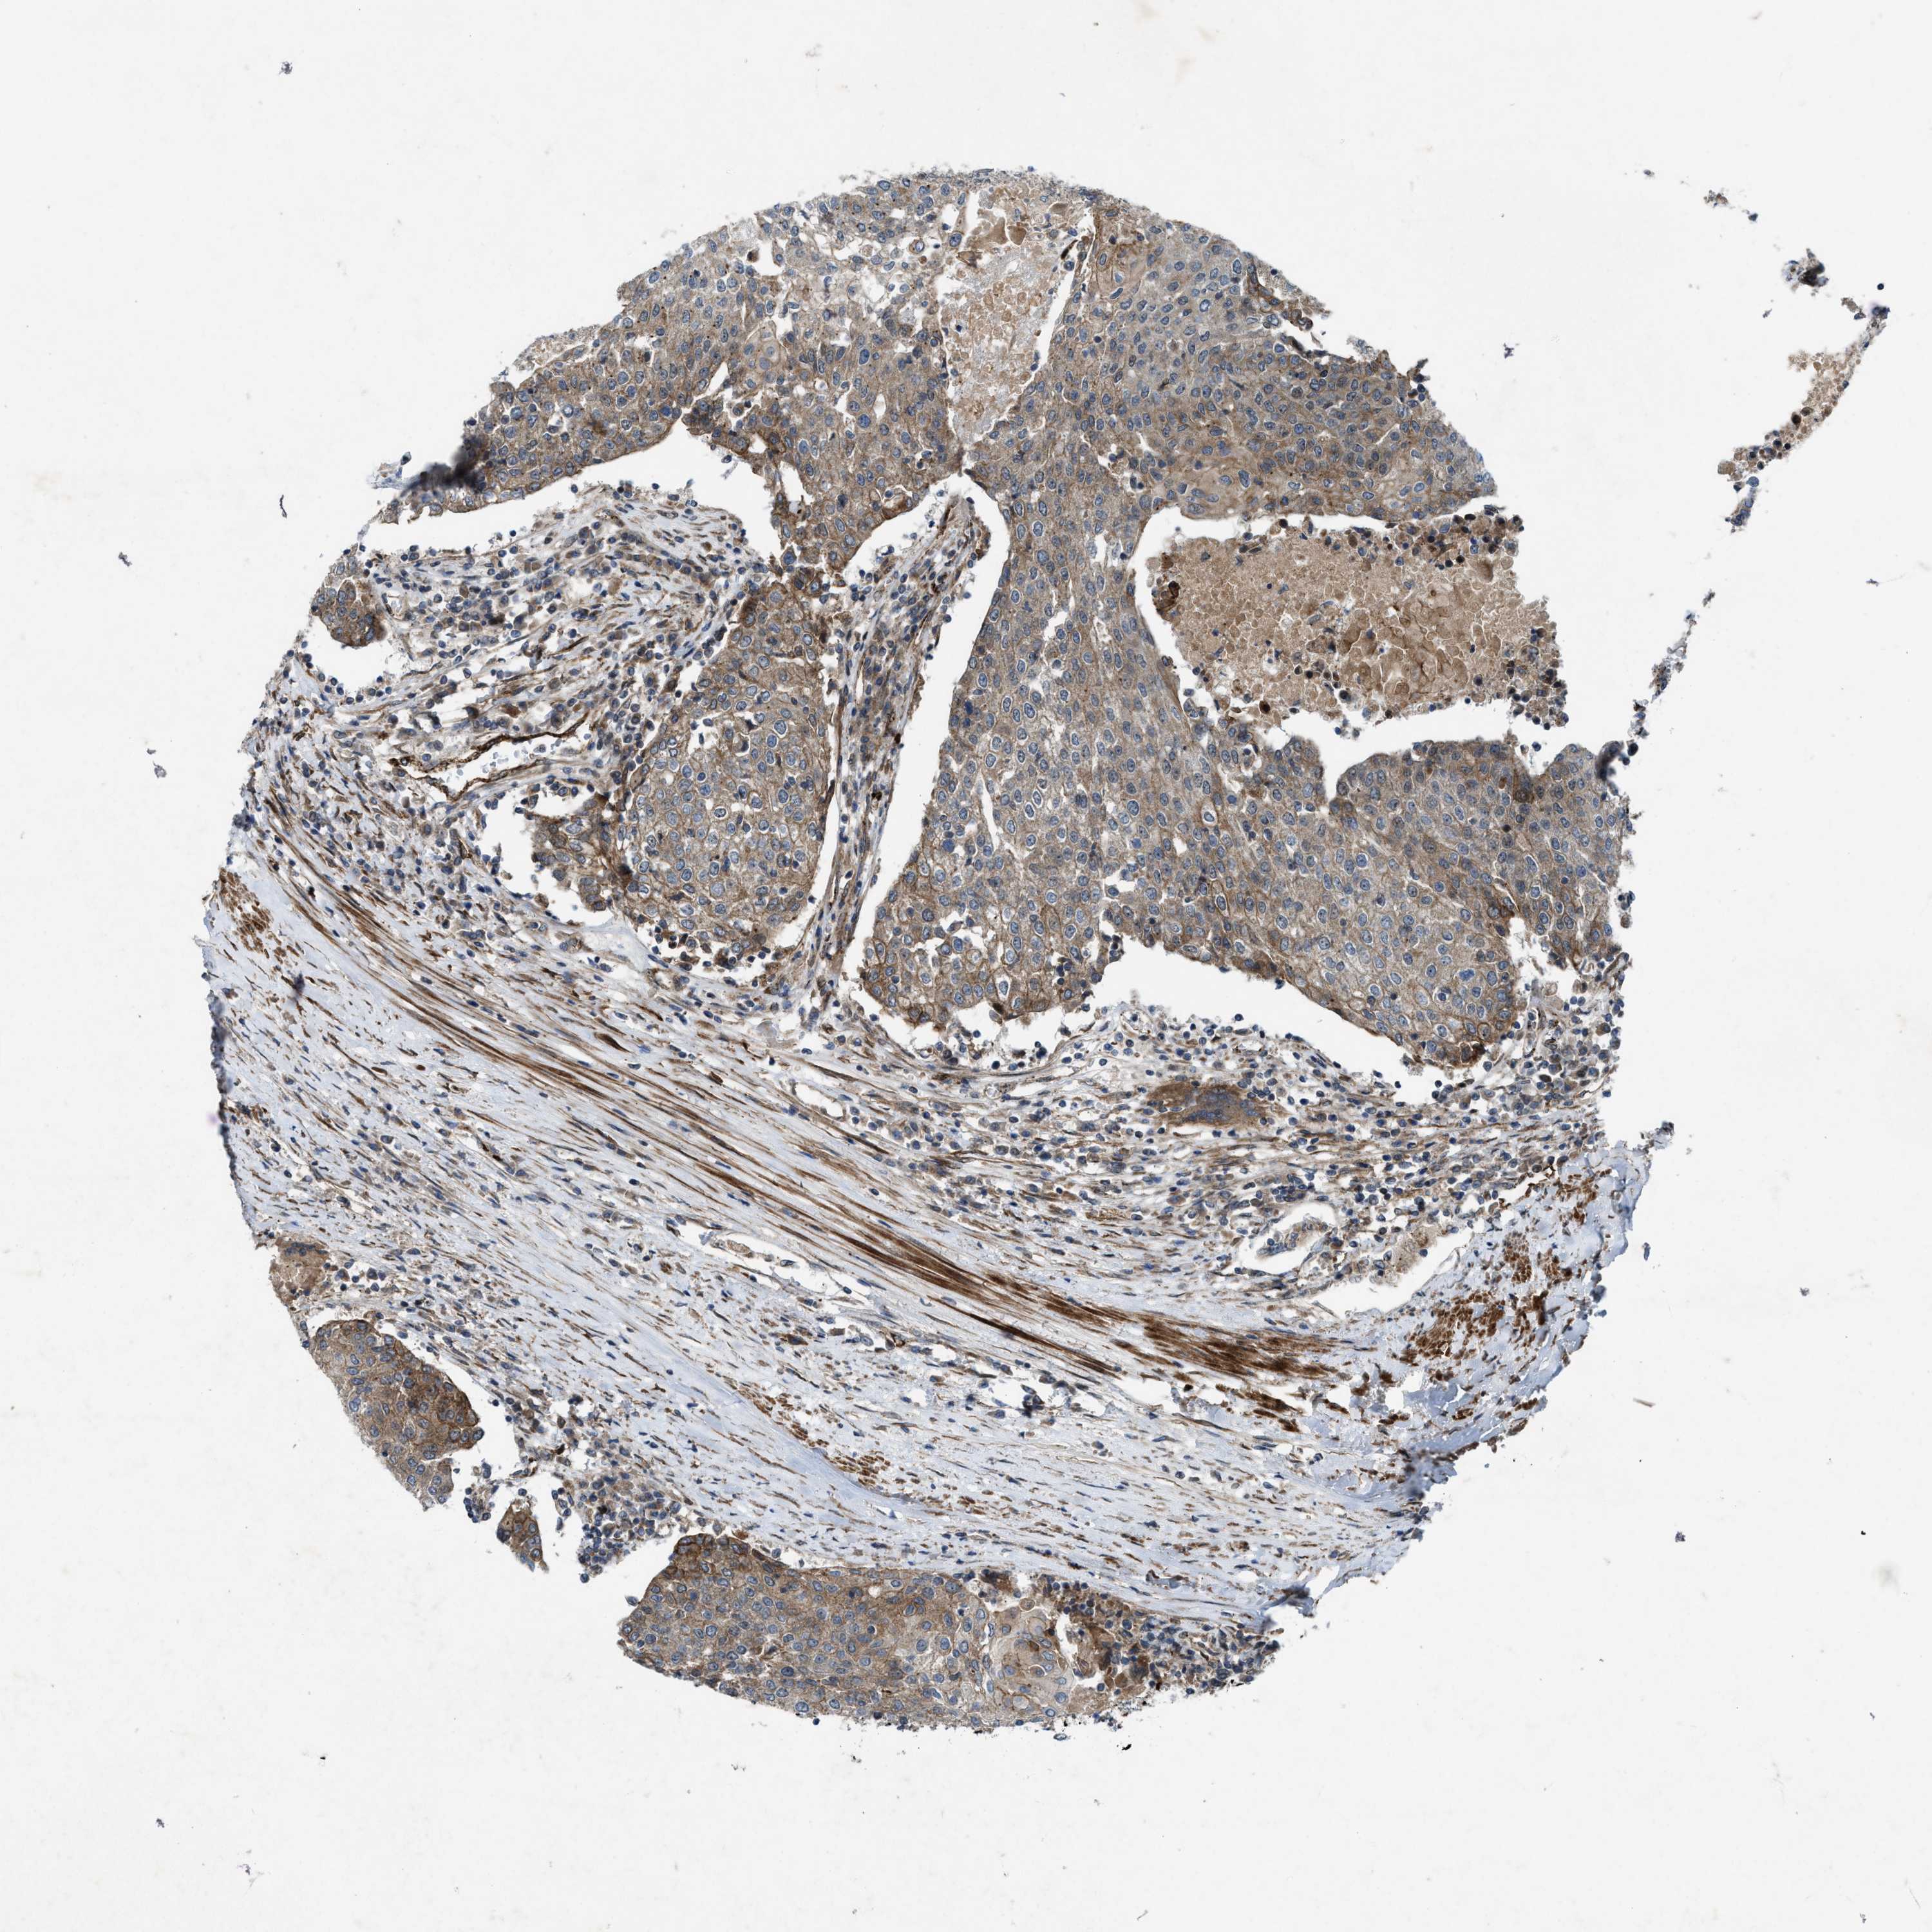

UROTHELIAL CANCER - Protein expressioni

A mouse-over function shows sample information and annotation data. Click on an image to view it in a full screen mode. Samples can be filtered based on level of antibody staining by selecting one or several of the following categories: high, medium, low and not detected. The assay and annotation is described here.

Note that samples used for immunohistochemistry by the Human Protein Atlas do not correspond to samples in the TCGA dataset.

Antibody stainingi

Antibody staining in the annotated cell types in the current human tissue is reported as not detected, low, medium, or high, based on conventional immunohistochemistry profiling in selected tissues. This score is based on the combination of the staining intensity and fraction of stained cells.

Each image is clickable and will lead to virtual microscopy that enables deeper exploration of all samples and also displays staining intensity scores, fraction scores and subcellular localization as well as patient and tissue information for each sample.

Antibody HPA019879

Antibody HPA020134

Antibody HPA029468

Staining

High

Medium

Low

Not detected

Intensity

Strong

Moderate

Weak

Negative

Quantity

>75%

75%-25%

<25%

None

Location

Nuclear

Cytoplasmic/membranous

Cytoplasmic/membranous,nuclear

Urothelial carcinoma, Low grade

Urothelial carcinoma, High grade